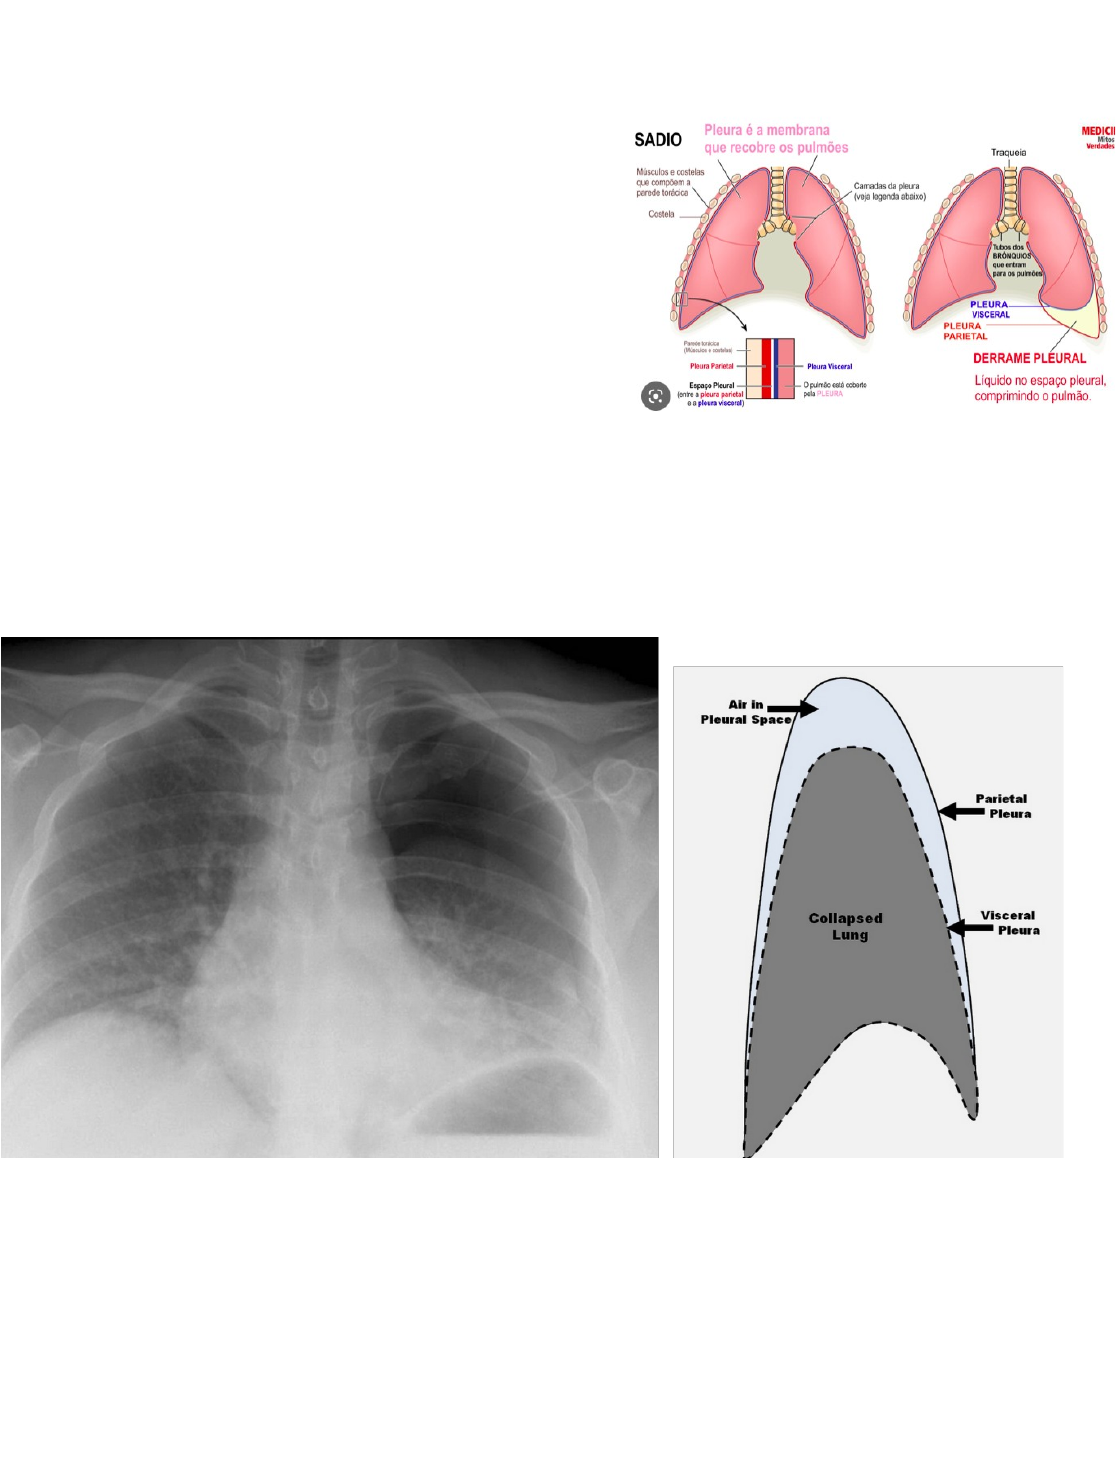

Pneumotórax X Derrame Pleural

Pleura

P. Visceral

P. Parietal

Pressão negativa no espaço pleural : contração do diafragma levando à expansão pulmonar

Pneumotórax

→ ar no espaço pleural

· Ar no RX é escuro

Derrame Pleural

acúmulo anormal de líquido no espaço pleural

→ transudato (pouca quantidade de proteína - Aumento de pressão)

→ exsudato (grande quantidade de proteína- Redução de drenagem)

→ livre ( se movimenta ) ou loculado (preso em alguma cavidade )

→ obliteração dos recessos costo-frênicos e cardiofrênicos, espessamento e líquido entre as cissuras, sinal do menisco, opacificação do hemitórax com desvio das estruturas do mediastino